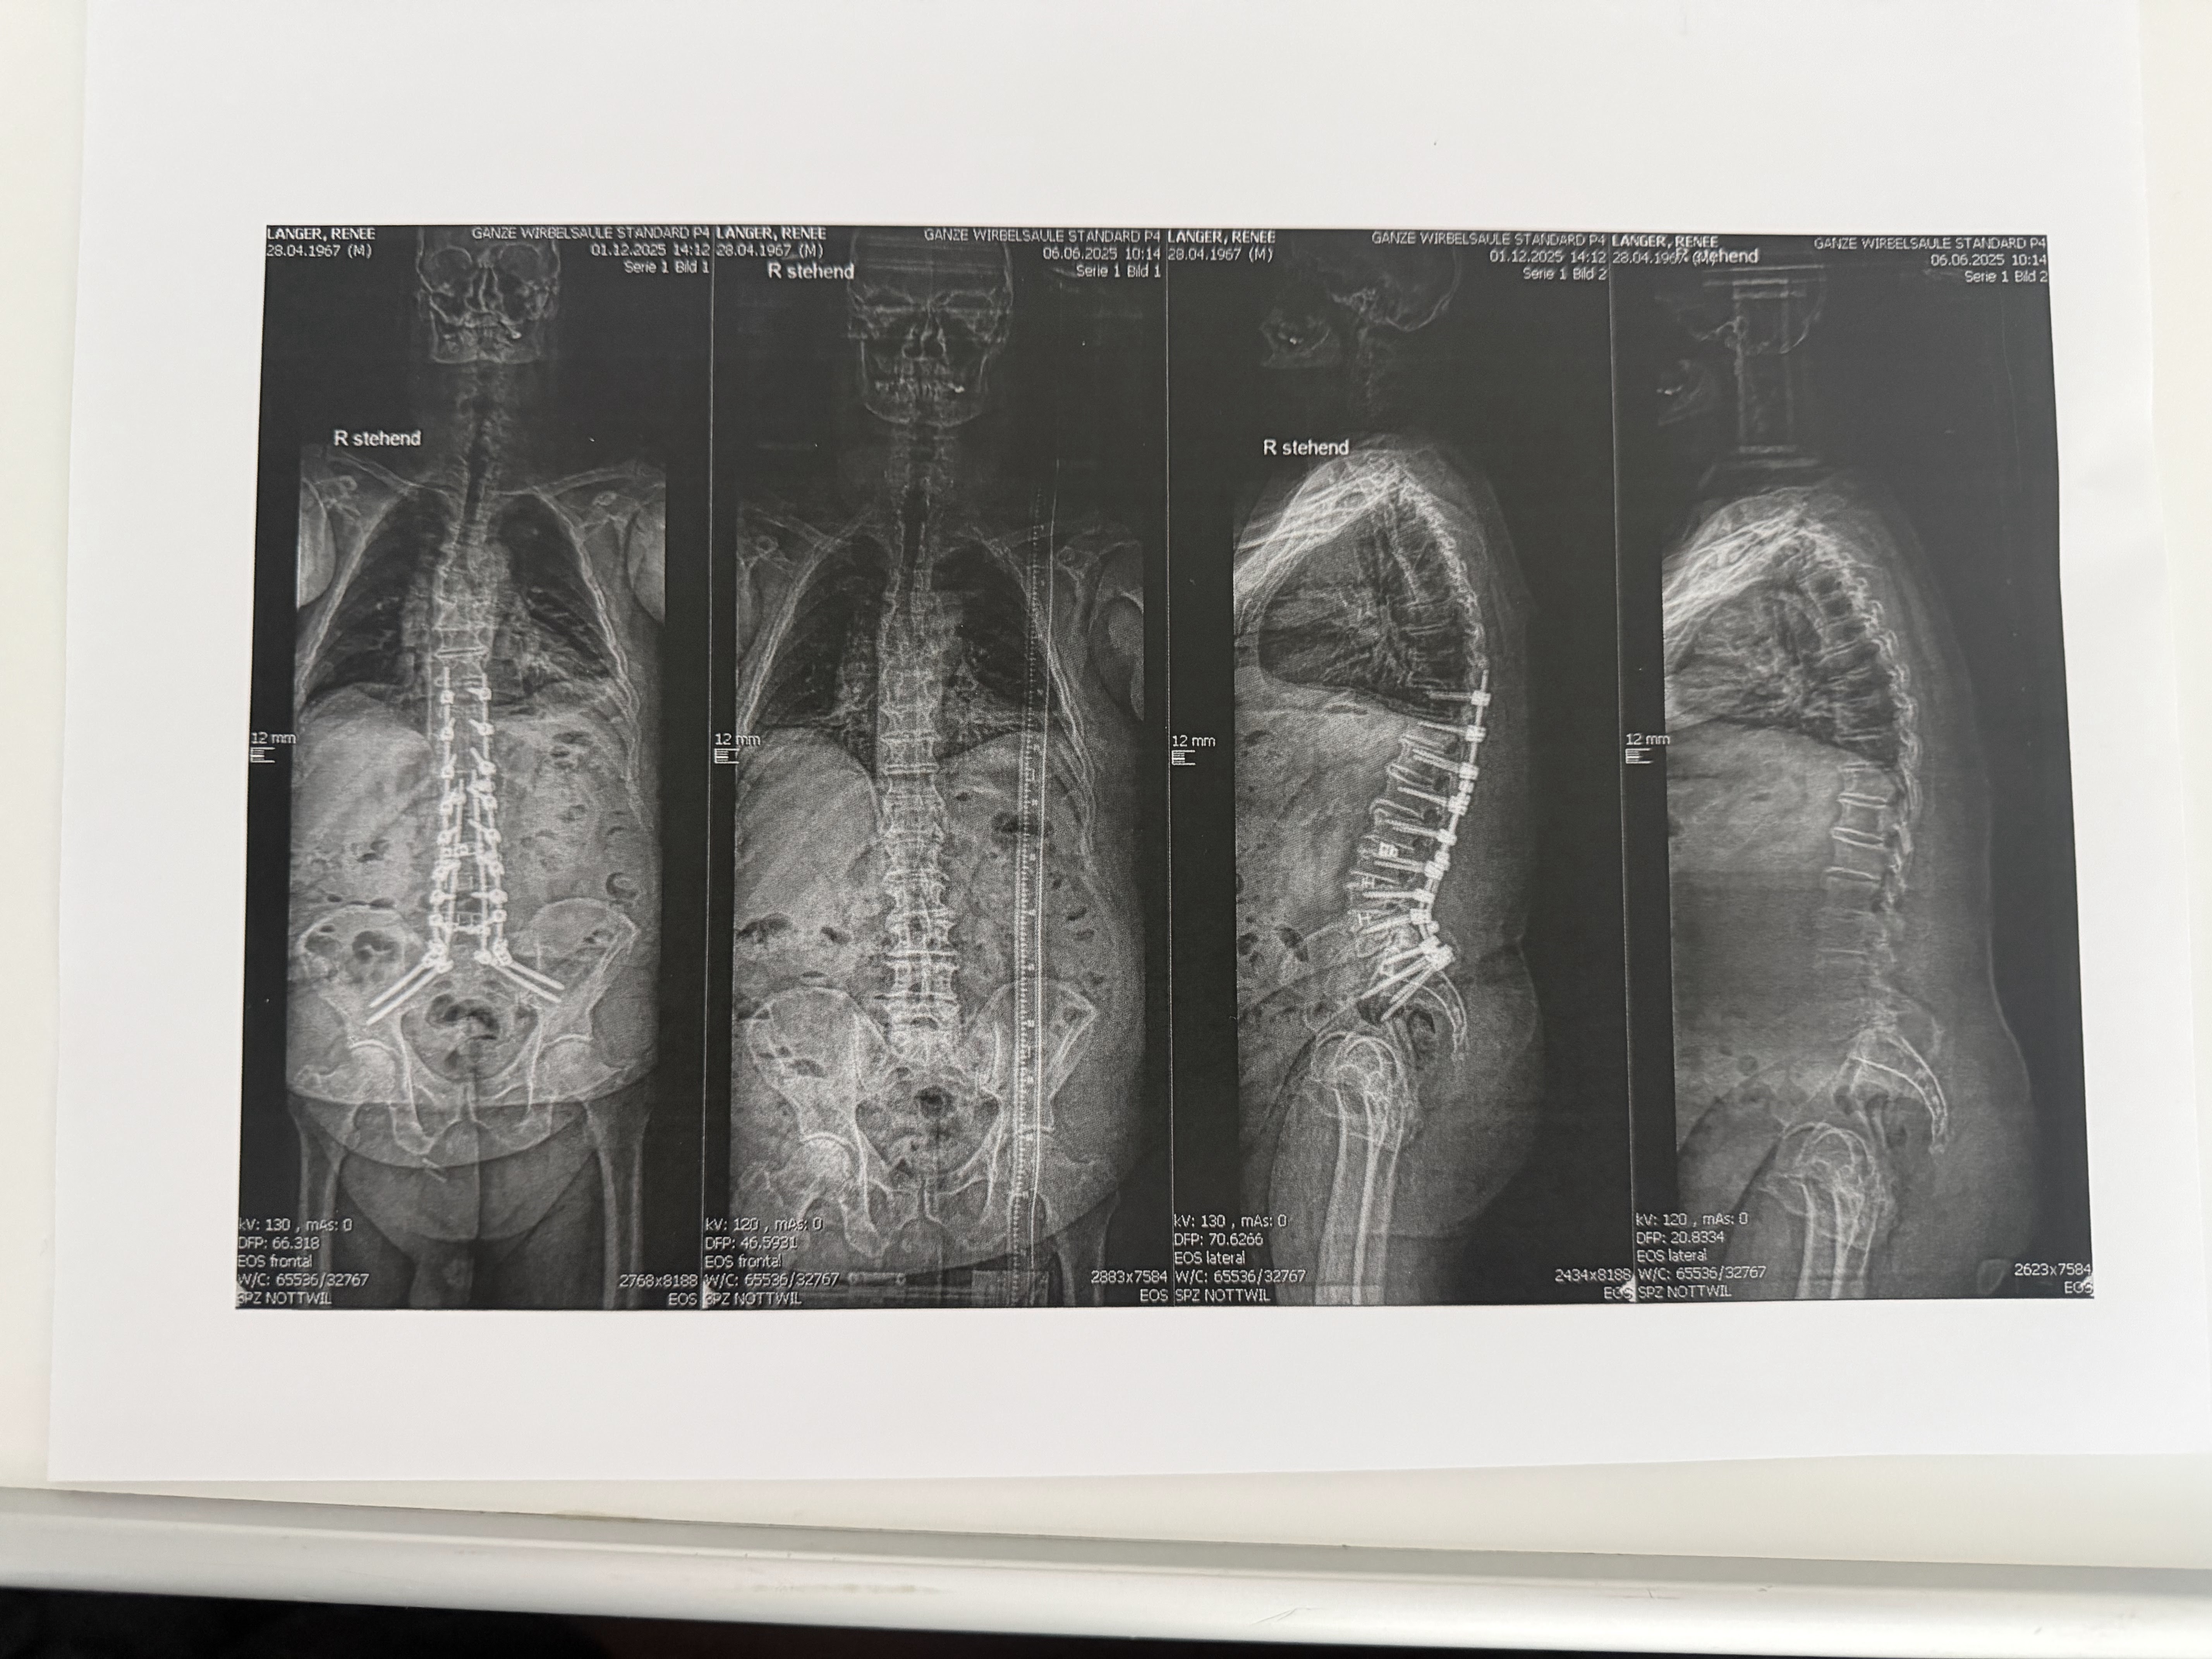

Und ich, Renee: Nach 40 Jahren harter Arbeit auf dem Bau musste auch ich meinen Körper aufgeben. Vier Rückenoperationen später und mit einer bleibenden Fusshebeschwäche schaffe ich kaum noch Wege ohne Rollstuhl. Mein Beruf, mein Stolz, mein Leben draussen – einfach weg.

Moi, Renee: après 40 ans de travail physique dans le bâtiment, mon corps a lâché. Après quatre opérations du dos et avec une faiblesse permanente du pied, je ne peux presque plus me déplacer sans fauteuil roulant. Mon métier, ma fierté, ma vie en plein air – tout a changé.